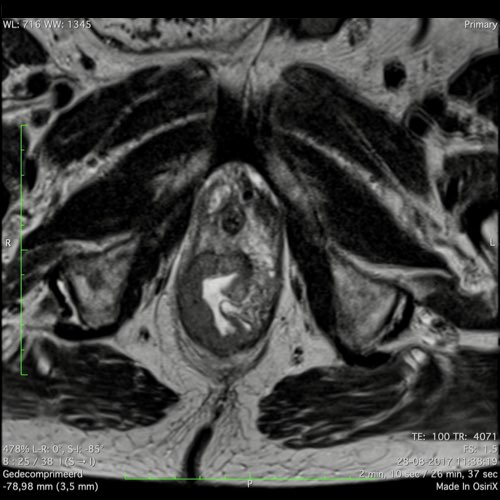

Hình ảnh

Các hình ảnh được cung cấp cho thấy ung thư biểu mô tế bào nhẫn với tình trạng dày lan tỏa thành trực tràng, hình ảnh bia bắn điển hình, và sự xâm lấn mỡ mạc treo trực tràng.